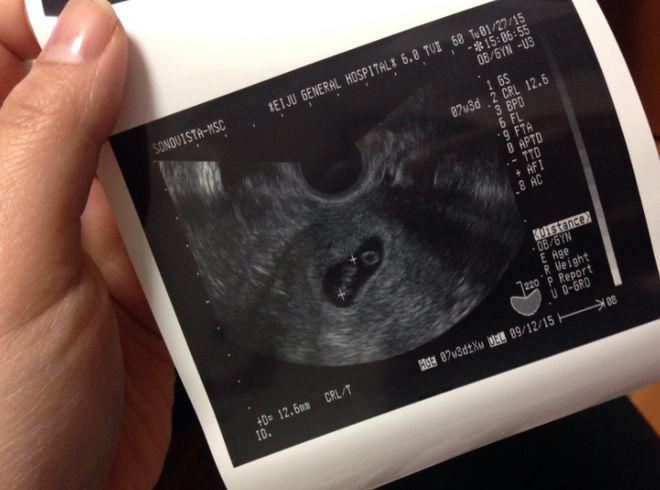

“可能性小”不代表“可能性为零”,为了您和宝宝的健康,最安全、最正确的做法就是立即联系您的产科医生,听从他们的专业建议,医生可能会让您去医院观察,或者安排一个B超检查来确认情况,这样您才能彻底放心。